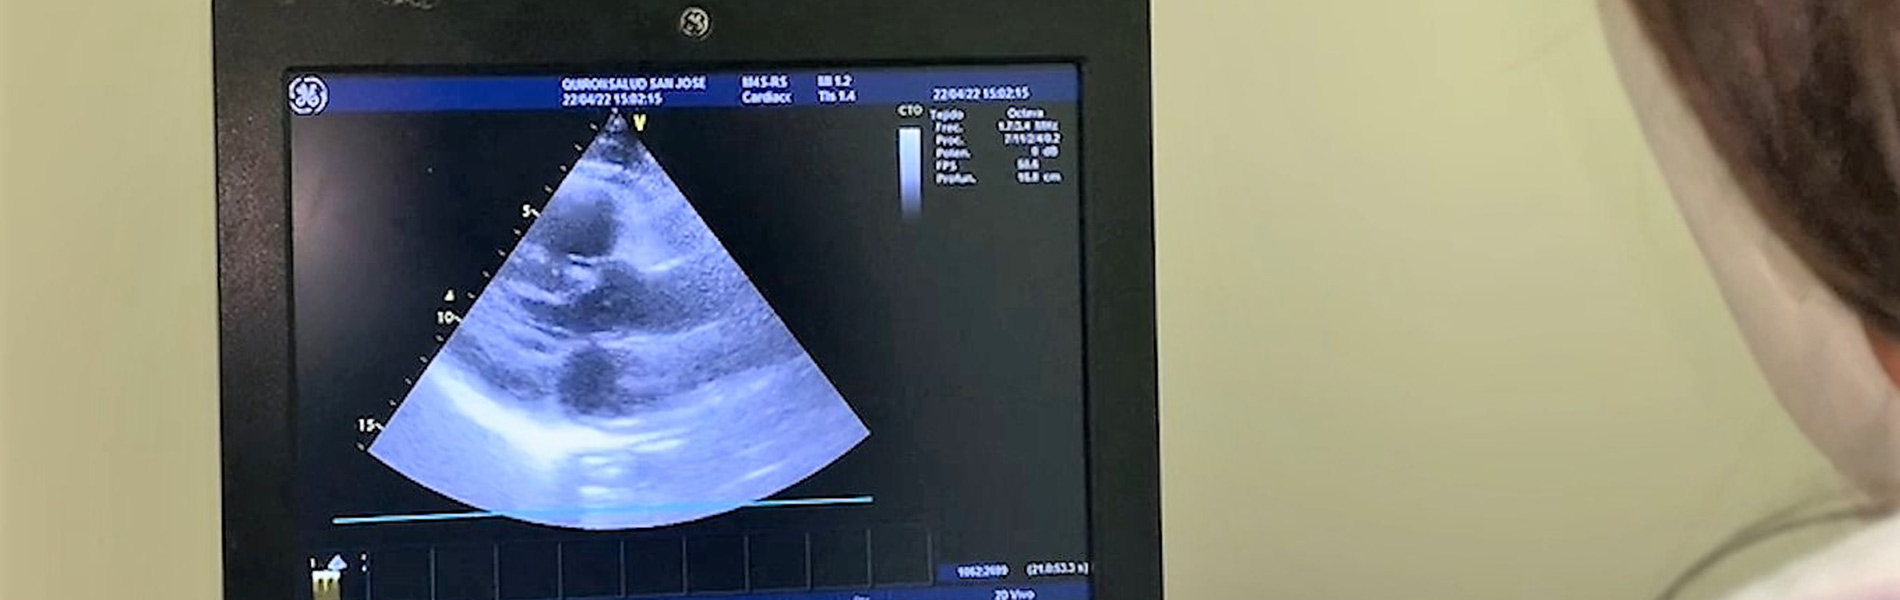

La doctora Esther Merino Lanza, especialista en Cardiología del Hospital Quirónsalud San José, da luz a estas respuestas y explica las claves de esta persistencia. «El covid persistente lo padecen pacientes en los que observamos una serie de síntomas aún después de que hayan superado la fase aguda de la enfermedad», explica Esther Merino.

Esther Merino señala que los pacientes con covid persistente deben acudir a revisión para que los facultativos médicos hagan un seguimiento de cómo va evolucionando la enfermedad. En los hospitales de Quirónsalud cuentan con un área especial.

La médico de Quirónsalud recomienda que aquellos pacientes que han tenido que ser hospitalizados, o que han padecido afecciones cardiovasculares mientras tenían la enfermedad, acudan a un facultativo médico que le realice un seguimiento.